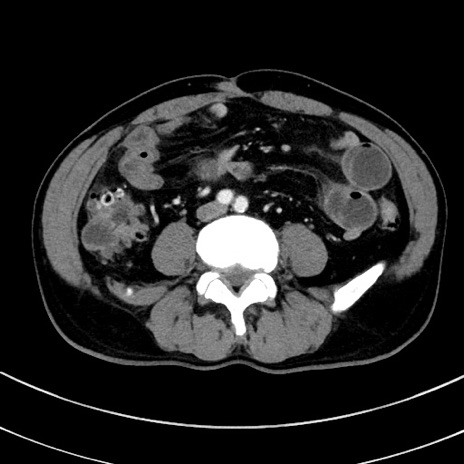

症例8(横断像)

【症例】 60歳代男性

【主訴】 黒色吐物

【現病歴】 4日前から嘔気自覚、2日前の朝食後にも嘔気あり、自分で手で嘔吐反射起こし嘔吐したところ血が混ざっていたため受診。

【既往歴】 5年前汎発性腹膜炎を伴う急性虫垂炎で手術、高血圧、前立腺肥大症、高脂血症

【身体所見】 腹部正中に手術癩痕あり 腹部平坦・軟圧痛なし膨満感あり

【データ】WBC 8400、CRP 4.54